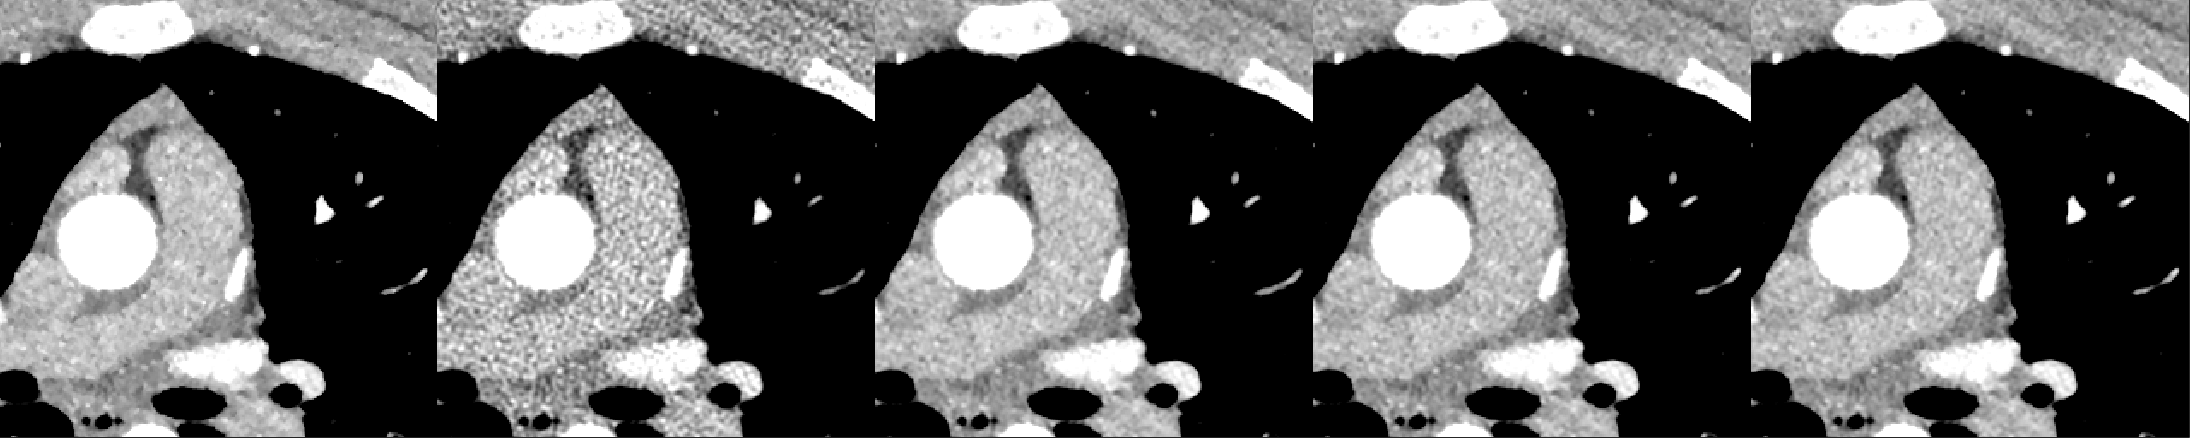

A cardiac FBP image was inferenced on the trained DL-MBIR network. Inference time for every network was between 4 and 6 seconds, and it goes up with the increase in the number of input channels. The MBIR version of the same exam was also available. Figure 3 shows a comparison, for 4 slices – LABEL:sub@fig:Image_10, LABEL:sub@fig:Image_50, LABEL:sub@fig:Image_90, and LABEL:sub@fig:Image_170 in the image volume, among MBIR image, FBP image, and the outputs of DL-MBIRZ𝐷𝐿-𝑀𝐵𝐼subscript𝑅𝑍DL\text{-}MBIR_{Z}, where Z=1, 3, 5𝑍135Z=1,\ 3,\ 5. Figure 4 shows a comparison, for the same slices in the image volume, among difference between images and the MBIR images. Figure 5 has a profile plot to show the comparison of DL-MBIRZ𝐷𝐿-𝑀𝐵𝐼subscript𝑅𝑍DL\text{-}MBIR_{Z} and FBP images w.r.t the MBIR images.

Refer to caption

(a)

(b)

(c)

(d)

Figure 3: Reconstructed image. (left to right): MBIR𝑀𝐵𝐼𝑅MBIR, FBP𝐹𝐵𝑃FBP, DL-MBIR1𝐷𝐿-𝑀𝐵𝐼subscript𝑅1DL\text{-}MBIR_{1}, DL-MBIR3𝐷𝐿-𝑀𝐵𝐼subscript𝑅3DL\text{-}MBIR_{3}, DL-MBIR5𝐷𝐿-𝑀𝐵𝐼subscript𝑅5DL\text{-}MBIR_{5}. LABEL:sub@fig:Image_10, LABEL:sub@fig:Image_50, LABEL:sub@fig:Image_90 and LABEL:sub@fig:Image_170 represent different slices in the image volume. WW/WL 450/0 HU.

Visually, all DL-MBIR images bear close resemblance to the MBIR images in figure 3. It is confirmed by the difference images in figure 4. In the profile plot of Figure 5, the DL-MBIR profiles closely follow that of MBIR.